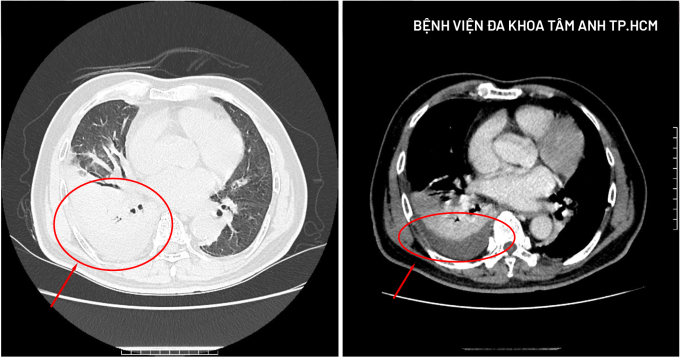

Ảnh CT phổi của ông Tỉnh ghi nhận tình trạng tràn dịch màng phổi (bên phải) và xẹp nhu mô phổi. Ảnh: Bệnh viện Đa khoa Tâm Anh